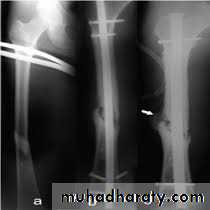

1- Delayed union

and

non-union need rigid fixation and bone graft .